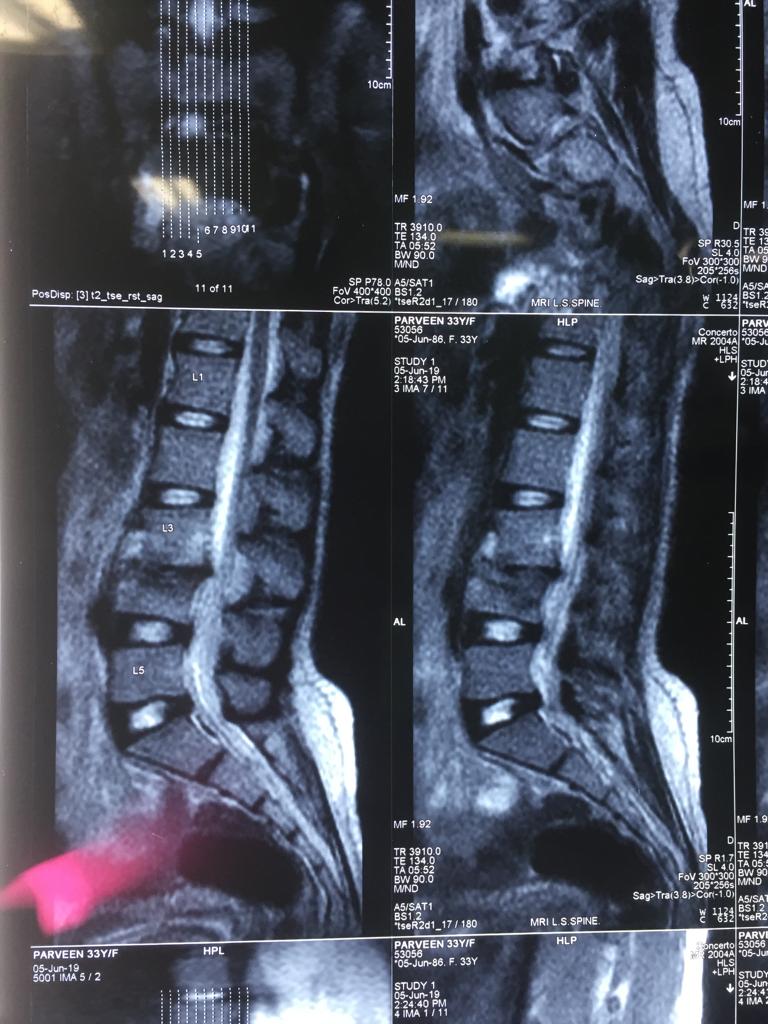

Cases